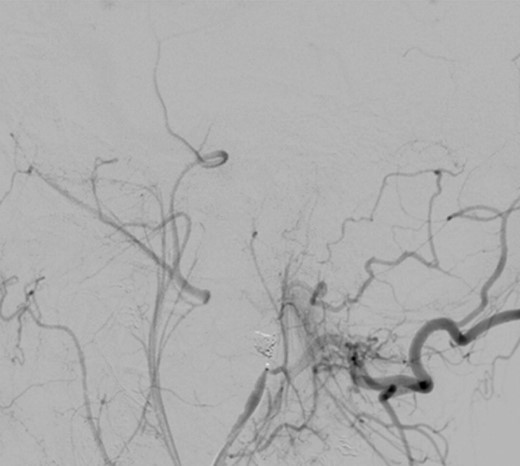

Under general anaesthesia, the right femoral artery was punctured and a guide catheter (5-Fr) was inserted. Selective runs were performed at the left common carotid artery and external carotid artery. The PA was detected at the bifurcation of superficial temporal artery and internal maxillary artery. Through a selective microcatheterization (1.7-Fr), coiling of the lesion and the bifurcation was performed. The final angiograms showed complete exclusion of the PA after coiling, with collateral flow networks that maintained distal patency of the proximally occluded vessels (Fig. 3).